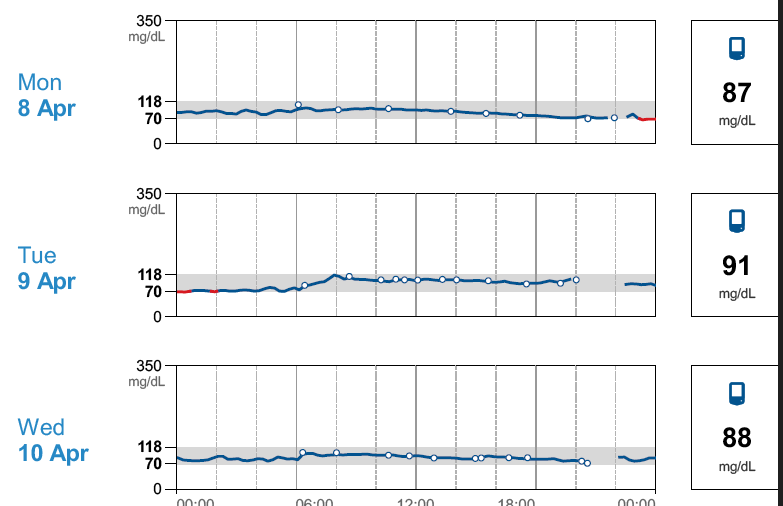

I Tried A Blood Glucose Monitor A Surprising Vegetable Spiked My

https://cdn.images.express.co.uk/img/dynamic/11/590x/secondary/i-wore-blood-glucose-monitor-month-diet-surprising-things-i-learned-vegetables-fruits-wholegrains-5067979.jpg?r=1700475448332